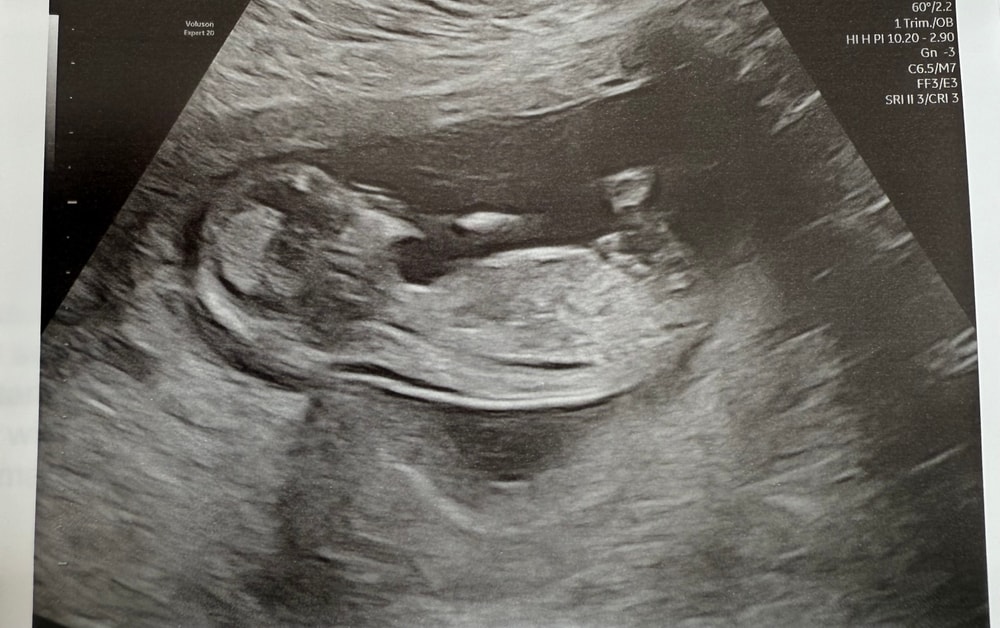

Наконец-то понемногу начинаю успокаиваться) первый скрининг прошел на ура. Сердечко бьется, кости носа визуализируются, твп 1,7 мм. Размеры от макушки до копчика 73,9 мм. Поставили срок 13н 3д, а по календарю был 12н 6д. Ждала второй триместр завтра, а оказывается уже три дня как😁 все время, пока врач смотрела, активно пиналась (или пинался) и пила околоплодные воды (около 15 минут😂). Врач смеялась, что первый раз видит, чтобы ребенок столько пил. Но сказала, что это хорошо, так он(а) тренируется глотать.

А еще показал(а) средний палец в экран😂 и недовольно потягивалась. Характером точно в меня😂